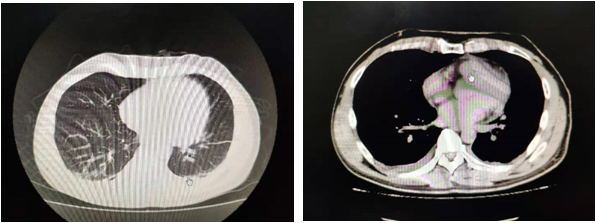

09.15

09.16出院